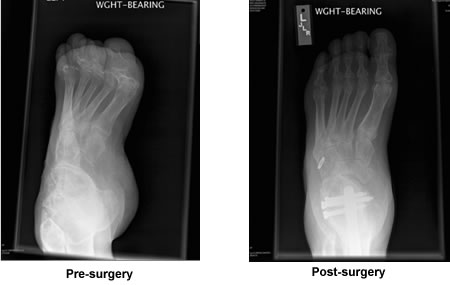

Muscular Dystrophy Foot Reconstruction

In July, 2008, I met Dr. Kenneth Leavitt at his office at New England Baptist Hospital. My left foot had been deformed since birth du e to Muscular Dystrophy. For the previous five years I could not walk 50 feet without excruciating pain. He took some x-rays, told me exactly what he was going to do, and how long I would be laid up. After three surgeries, I walked out of rehab with the help of crutches.

Last month I walked two miles on long beach in Gloucester without pain, something that I love, but had not been able to do in six years. Thanks to Dr. Leavitt and his colleague Dr. Talmo.